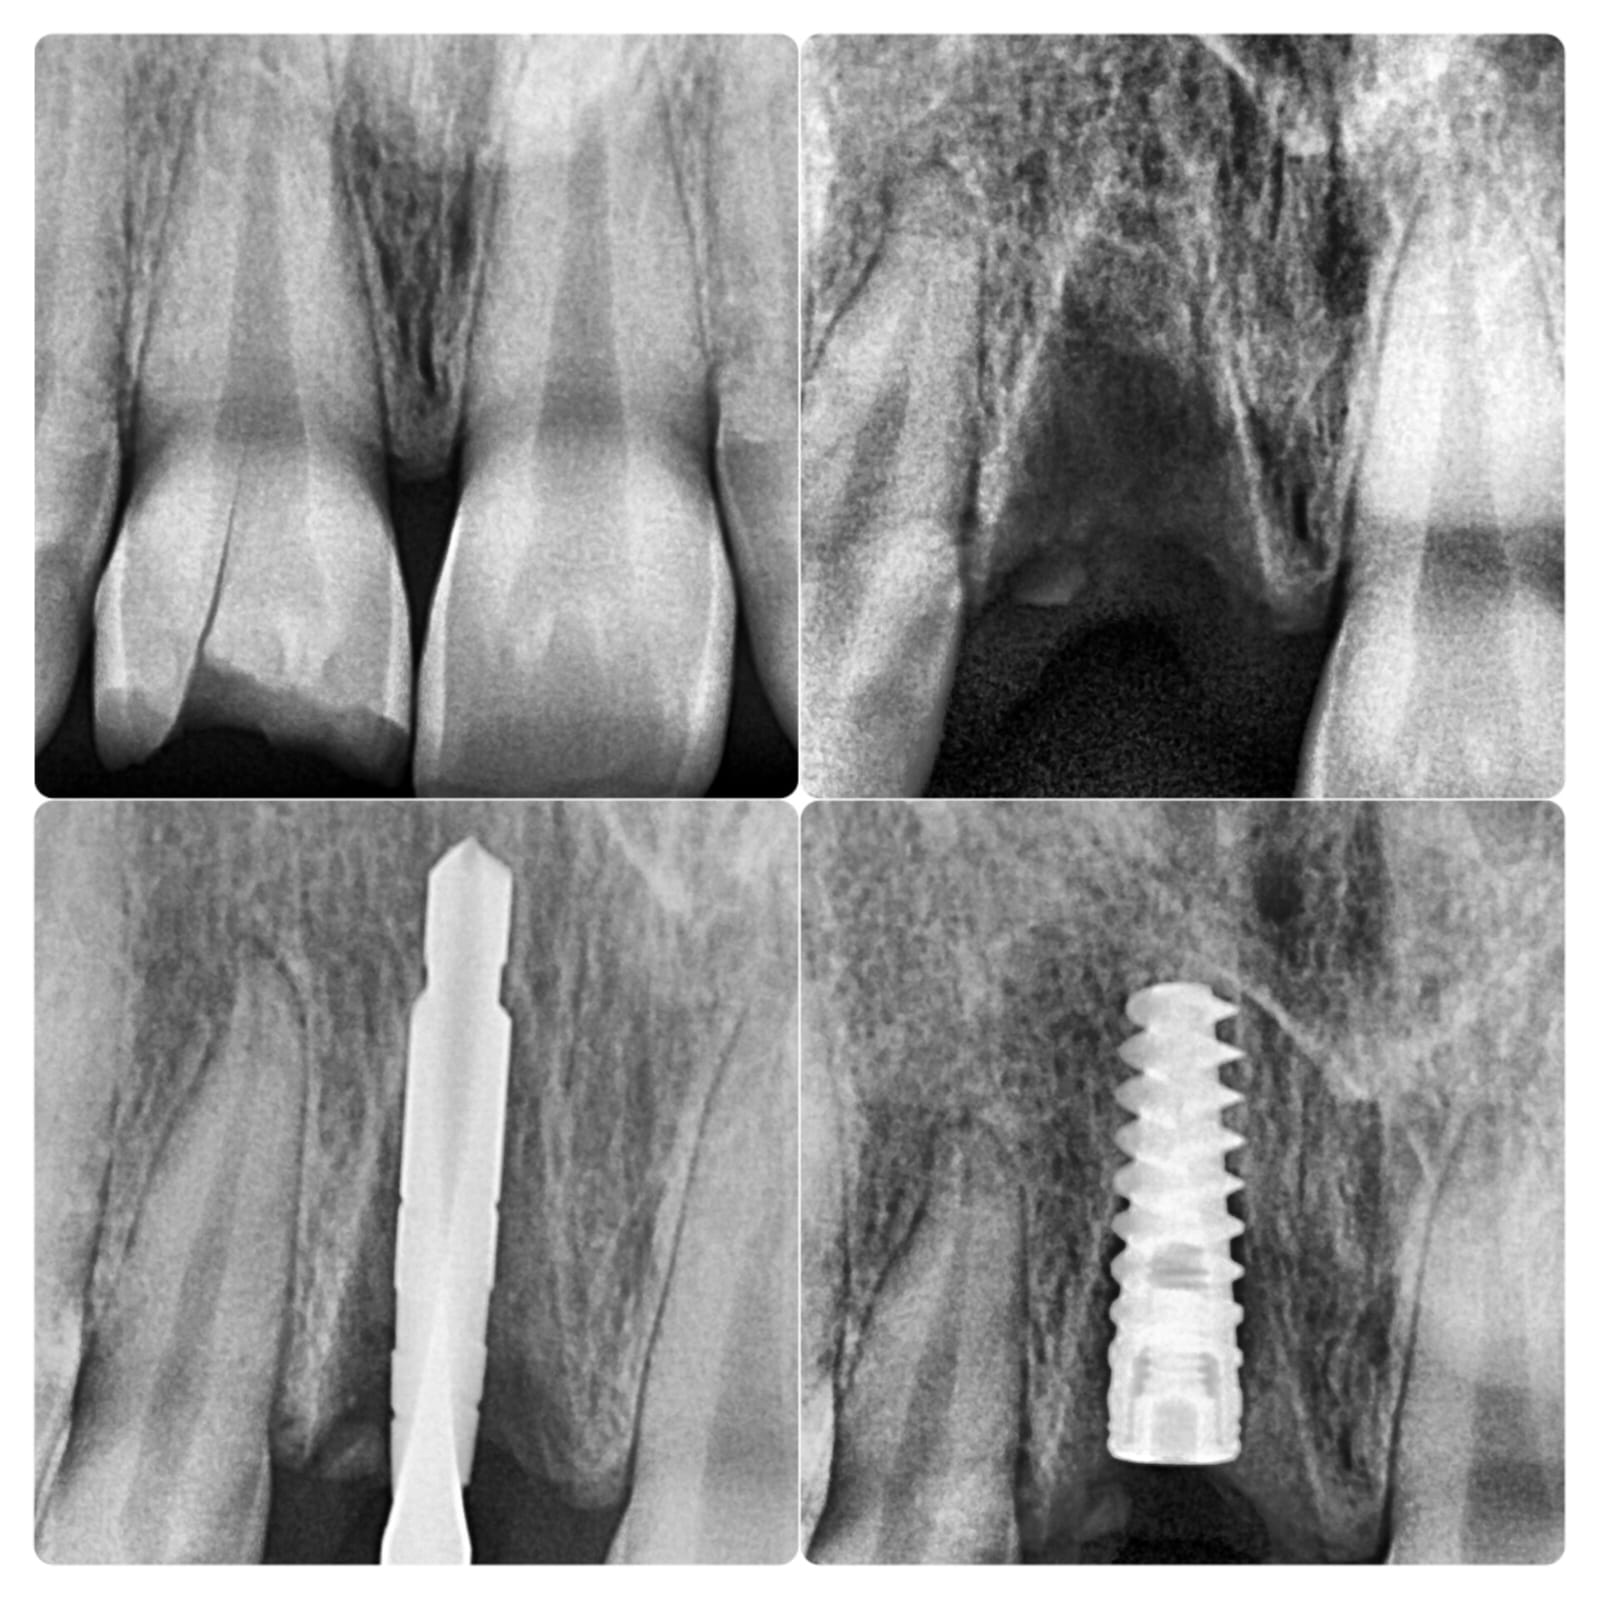

Photo Gallery